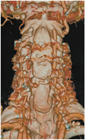

1. 頭蓋頚椎、頚胸椎、胸腰椎の各移行部での脊椎損傷は他の臓器との重なりが多く、単純X線では見落とされることがあり、CTによる評価が推奨される。